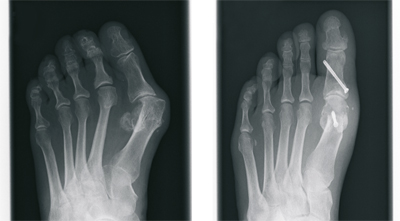

The Hallux valgus (balltoe)

Surgical correction without the presence of pain is not advisable from a purely cosmetic point of view. However, In case of pain in the big toe, the operative procedure is the only permanent therapeutic option.

After extensive examination, consideration of individual needs, as well as analysis of the X-ray images, the treatment is determined. Different internationally recognized surgical procedures are used. We use modern plates and titanium screws.